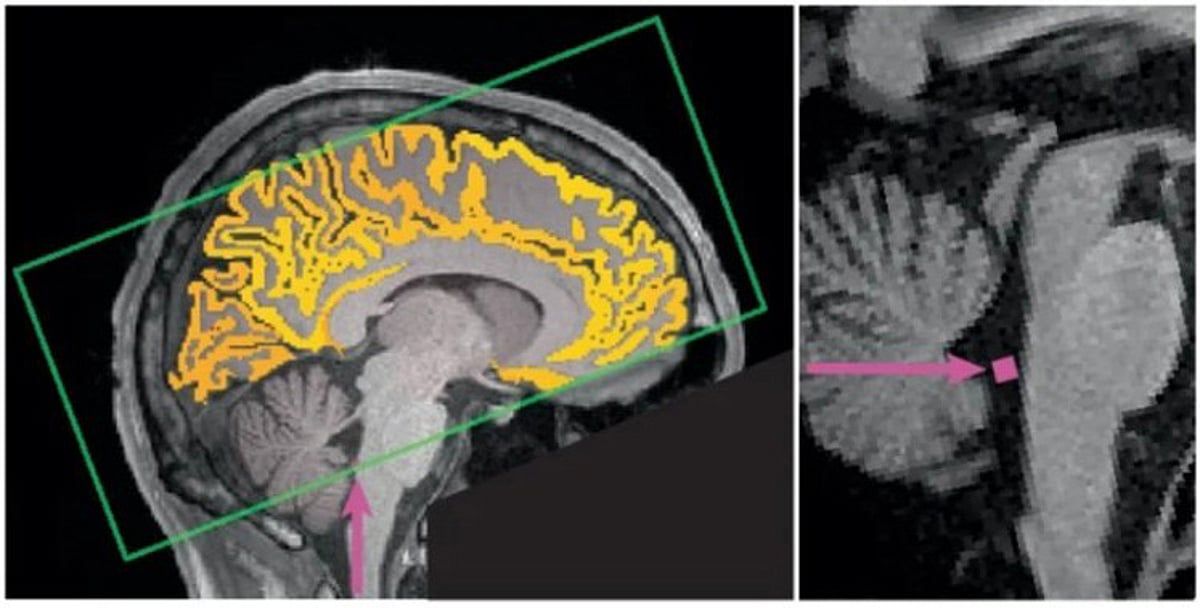

وأوضح "باهمام" في تدوينة عبر حسابه على منصة إكس، أنه عند قلة النوم تظهر لدى الإنسان فترات من ضعف الانتباه والتركيز، وخلالها يقوم الدماغ بدفع السائل الدماغي الشوكي إلى الخارج في محاولةٍ للتخلص من السموم، وهي عملية تحدث عادة أثناء النوم فقط.